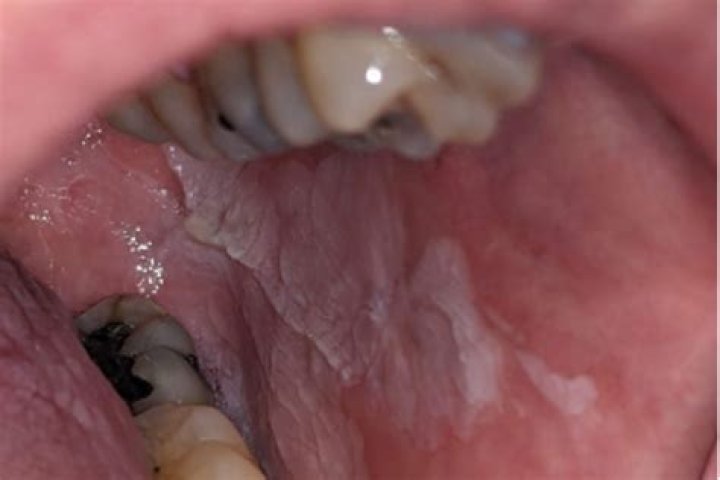

Oral hairy leukoplakia is a benign, asymptomatic, white, hyperkeratotic lesion affecting primarily the lateral border of the tongue, unilaterally or bilaterally (Figures ​1 and ​2); but rarely it may occur elsewhere in the mouth.

It causes fuzzy white patches, often on the sides of the tongue, that look folded or ridged. They're not painful and cannot be brushed or scraped away. Antiviral medicines, or treatments applied directly to the patch, may be prescribed to treat hairy leukoplakia.